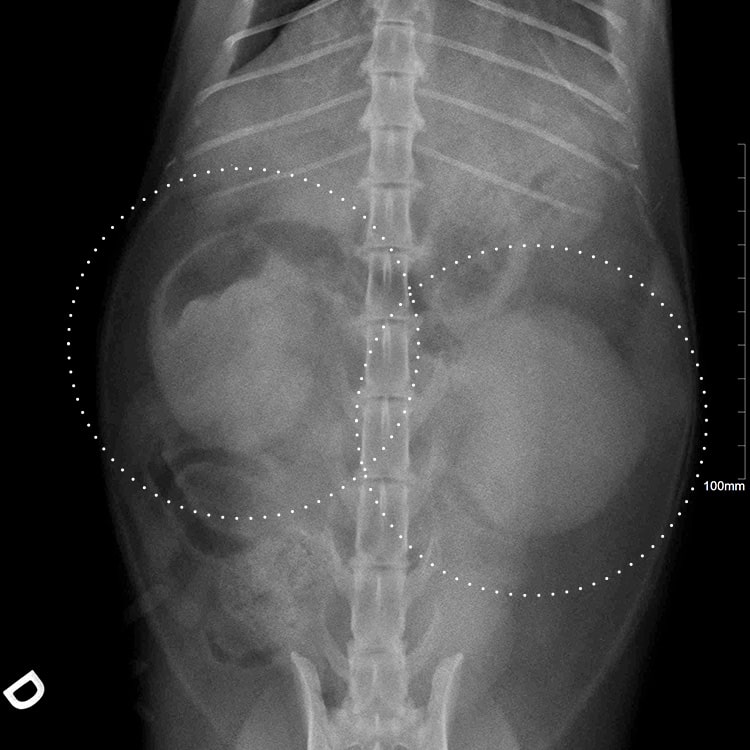

Radiographie d’un lymphome rénal chez un chat avec infiltration des deux reins par les cellules tumorales

Le lymphome rénal concerne les reins. La tumeur peut être d’origine rénale (en prenant naissance dans l’organe) ou d’origine digestive (suite à la dissémination d’un lymphome digestif).

Les chats atteints sont présentés avec des signes d’insuffisance rénale (une défaillance des reins qui ne filtrent plus correctement le sang).

• Une augmentation du volume des reins, qu’il est possible de sentir lors d’une palpation abdominale.